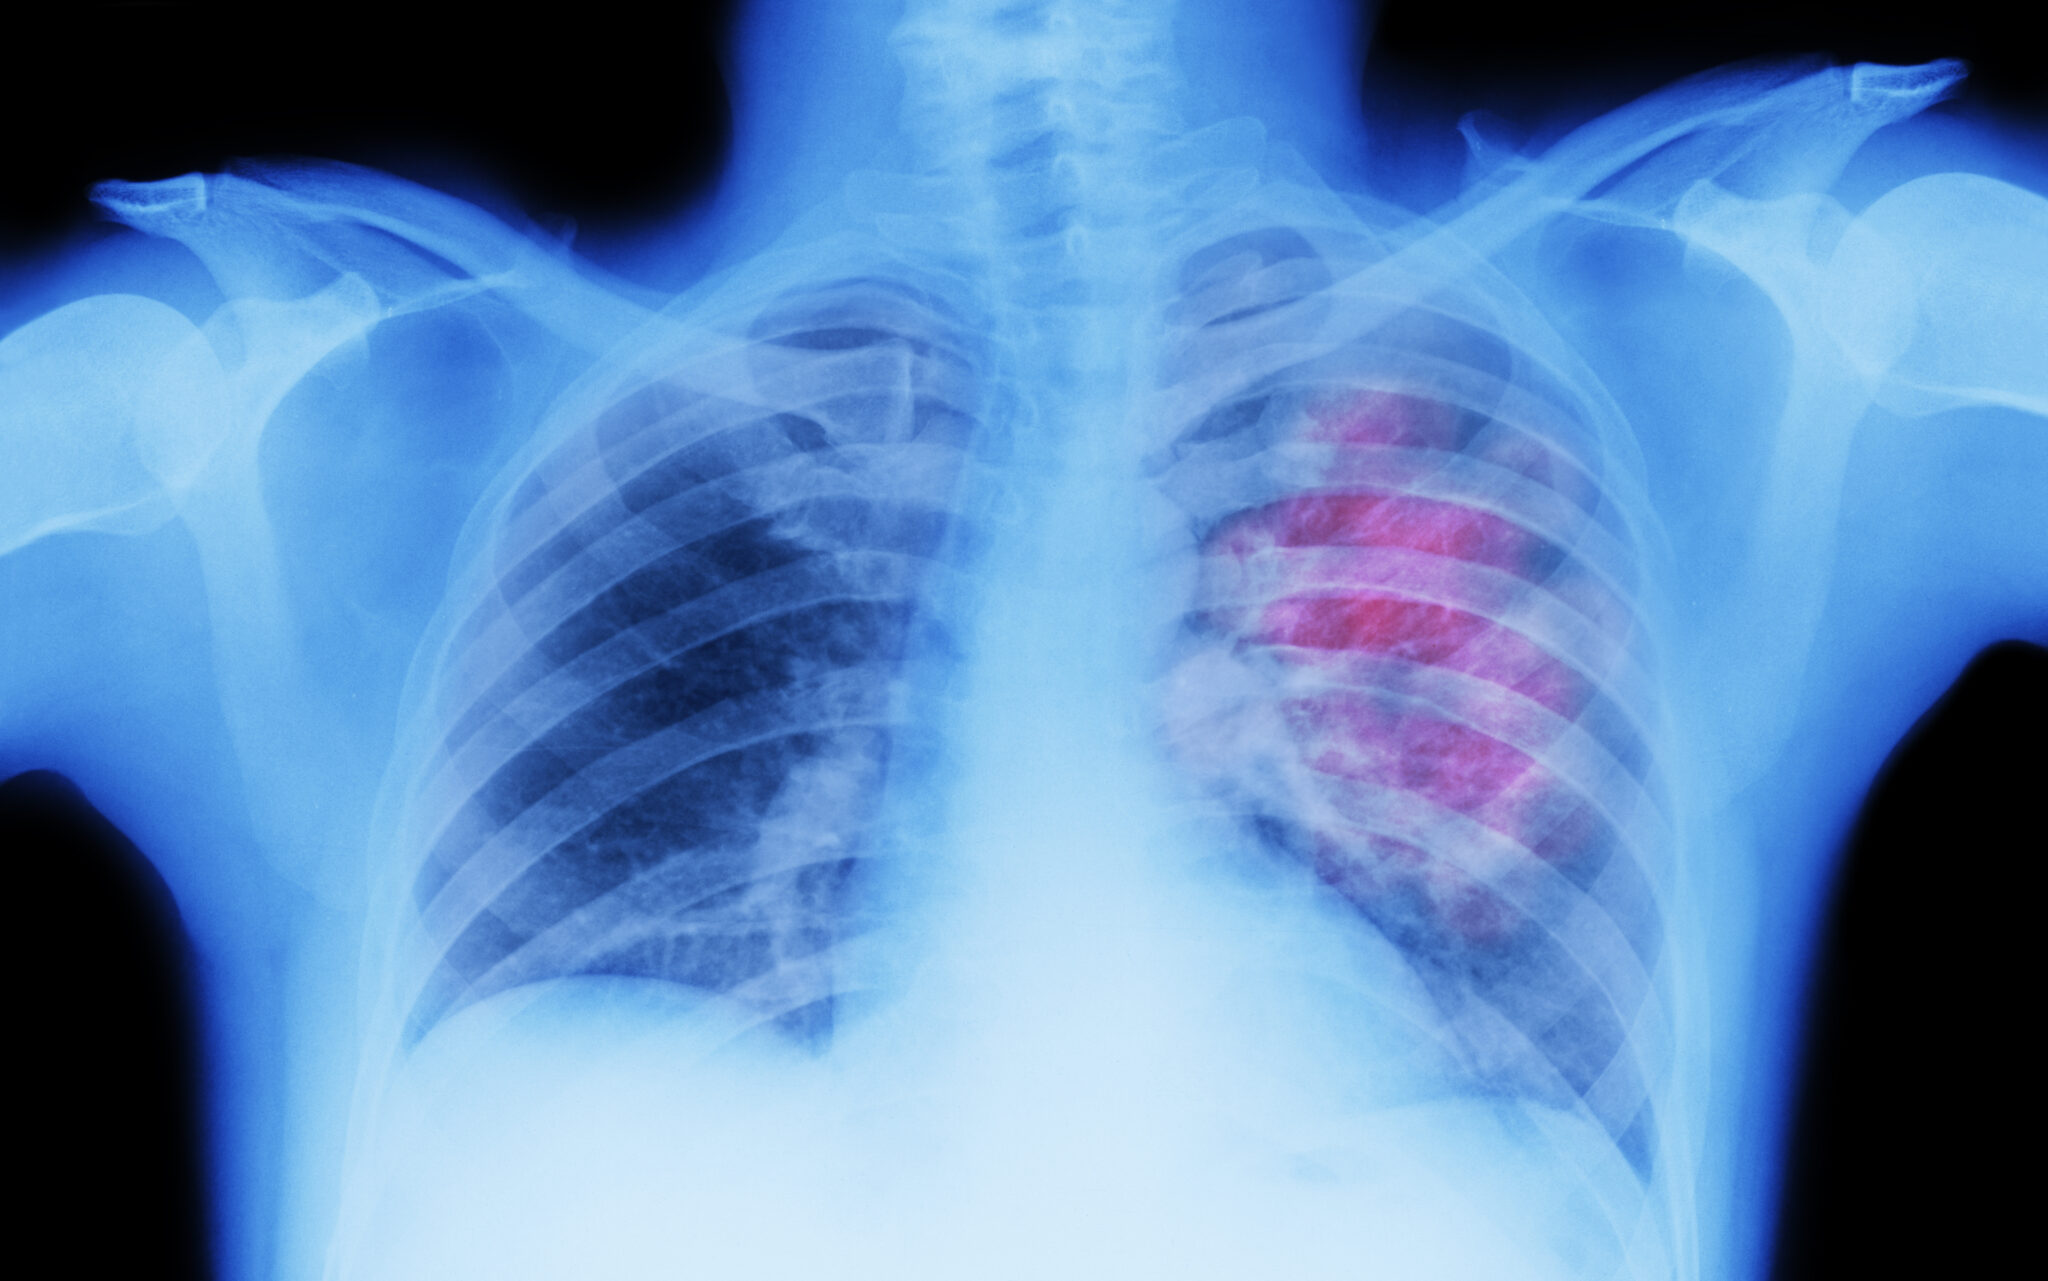

Lung cancer is categorized into four stages, labeled stage I through stage IV. Stage IV is the most advanced, and unfortunately, this is when many people first receive their diagnosis. If you or someone close to you has just learned they have stage 4 lung cancer, it likely means the cancer has spread — or metastasized — beyond one lung to other areas of the body.

At this stage, cancer cells may be found in the opposite lung, nearby lymph nodes, or even in distant organs such as the bones, brain, or liver. This spread affects treatment planning, symptoms, and overall outlook. Choosing a cancer center or hospital located in your area can relieve stress and worry when thinking about whether your diagnosis is curable, and understanding what stage IV really means can help you have more productive conversations with your care team and prepare for what’s next.